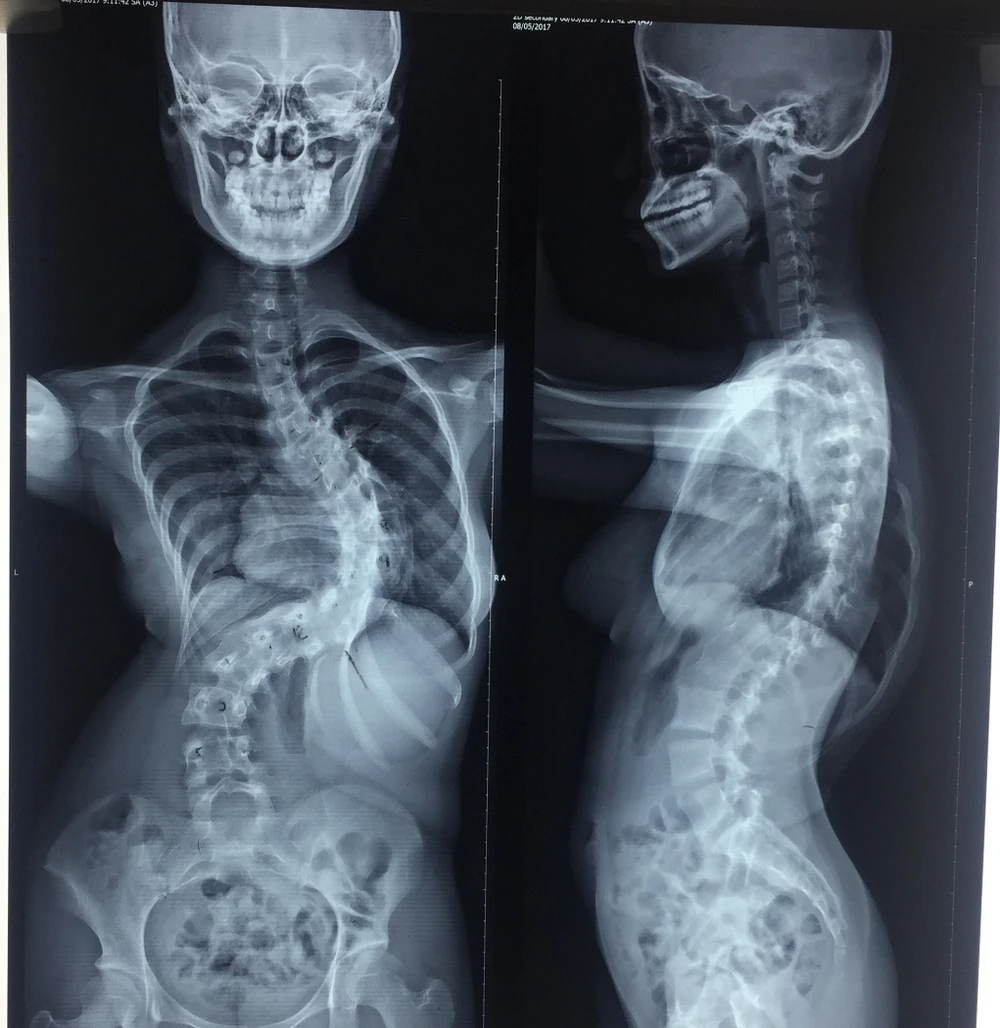

Kết quả chụp phim X-quang cho thấy cột sống của nữ sinh cong vẹo lớn. Ảnh: H.LAN

Bệnh nhân là một nữ sinh 15 tuổi, quê Kiên Giang bị mắc hội chứng Marfan rất nặng khi cột sống của em bị cong đến ba vùng, vùng nặng nhất cong đến 110 độ. Các bác sĩ BV Trưng Vương chẩn đoán hội chứng trên đã ảnh hưởng đến các chức năng hô hấp, tim mạch, suy dinh dưỡng... của bệnh nhân rất nhiều.

Bệnh nhân đã được nắn chỉnh hàn xương, bắt 21 ốc chân cung, bốn thanh nối dọc và ngang để nắn chỉnh lại cột sống. Trong quá trình mổ, các bác sĩ đã sử dụng máy lọc máu hoàn hồi có khả năng lọc lại lượng máu đã mất để truyền lại cho bệnh nhân nên hạn chế tối đa lượng máu chảy. Ca mổ đã nắn chỉnh được 64% cột sống cho nữ sinh, chỗ cong nhất từ 110 độ giảm còn 40 độ. Chiều cao của nữ sinh cũng tăng lên được 7cm, từ 1m48 lên 1m55. Hiện nữ sinh đã ngồi dậy và đi lại được.